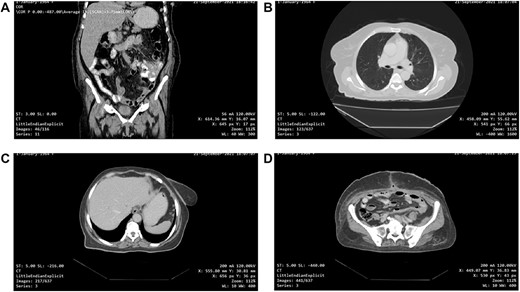

One-month post-operative computed tomography (CT) scan of the chest/abdomen/pelvis revealed: clear lung fields free of metastasis/lymphadenopathy, liver free of metastasis, no retroperitoneal/pelvic lymphadenopathy, no fluid levels near the surgical intervention field, no masses or signs of relapse/recurrence, and kidneys/spleen/genitourinary system are normal (Fig. 6A–D).

(A, B, C and D) One-month post-operative CT scan of the chest/abdomen/pelvis revealing a coronal view of the abdomen and pelvis/lung/liver/surgical site/pelvis free of tumour spread/metastasis/relapse.